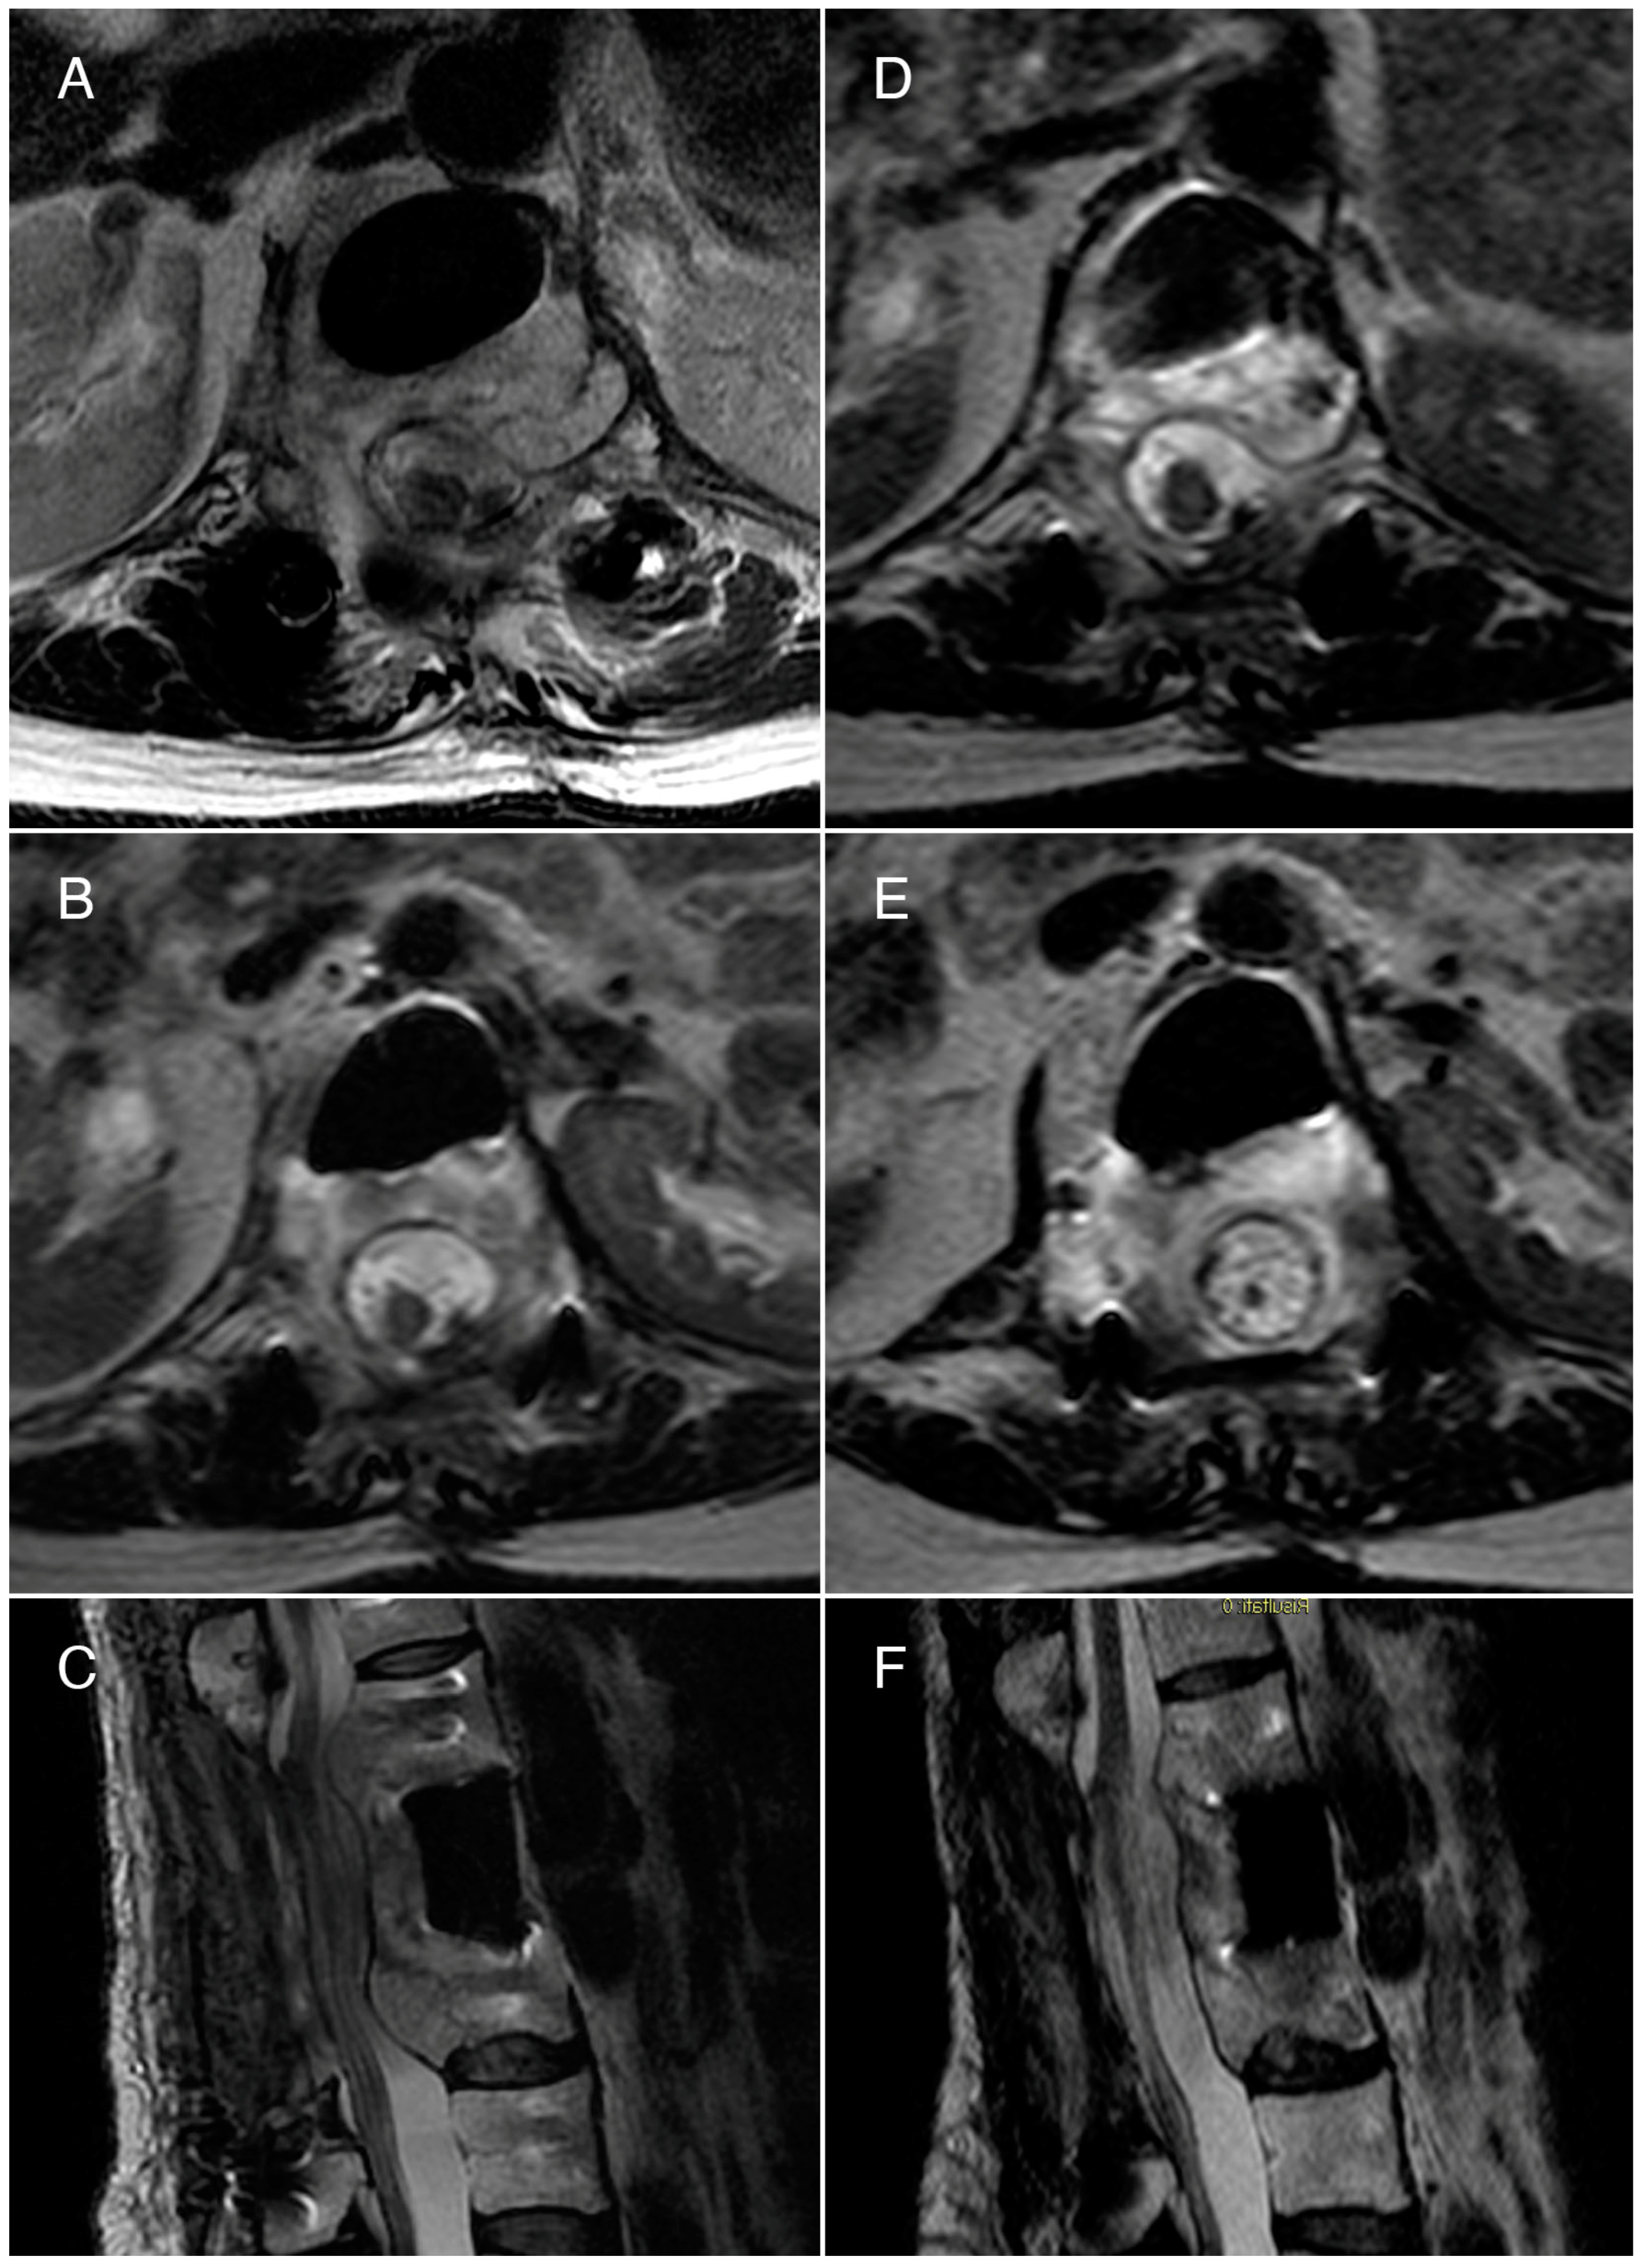

Due to the multiple recurrences, significant neurological symptoms, and the failure of various treatments, our team decided to enroll the patient in an electrochemotherapy trial. She received two treatments of electrochemotherapy with bleomycin at T12, L1, and L2 over four months, with no adverse events. The electrochemotherapy was performed by positioning six parallel needles adjacent to the vertebral bodies (two for each level) following the standard operating protocol for ECT as previously described [16,23,24]. For this patient, due to the presence of hardware and prothesis, a longer procedure time (a total time of 2 h and 45 min) and general anesthesia were required. The patient was intubated with low flow oxygen (<2 L/min) to reduce the risks of lung damage; before 15 mg/m2 of bleomycin were infused (2–3 min), clinicians made sure the FiO2 was under 30%. Eight minutes after infusion, pulses were applied. Two months after the initial treatment, MRI showed no significant changes compared to pre-electrochemotherapy. The treatment was repeated after four months with the same modalities, and a reduction in the lesion’s size was noted seven months after the second ECT, particularly in its intracanal component (Figure 2).

Figure 2.

Case 1: T2-weighted MRI scans. (A,B) Axial views and (C) sagittal view performed before the first ECT treatment. The axial view at the L2 level shows a hemangioma causing compression of the dura and the cauda. The sagittal view reveals the hemangioma’s extensive invasion into the epidural space, both above and below the surgically removed L1 vertebral body, at the levels of T12 and L2. (D,E) Axial views and (F) sagittal view performed 12 months after the first ECT show a reduction of the compression caused by the hemangioma.

The radiological results were associated with improved clinical outcomes, in particular pain reduction, and no adverse events were reported.